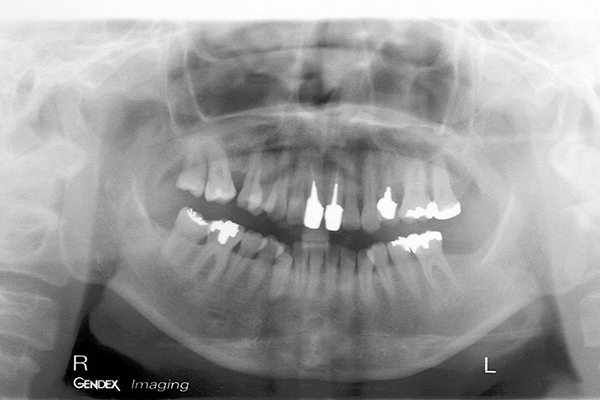

主訴は「全ての歯を綺麗に治したい」とのことで来院されました。診断の結果、複合的な問題が見つかり、歯周病治療、矯正治療等複数の治療を約3年ほど順番に進めていきました。最終的には歯の色味も回復させることができ、患者さんにも満足していただけました。

| 患者 | 45歳 女性 |

|---|---|

| 主訴 | 前歯が取れた。 |

| 診断 | このケースはかなりひどい叢生があり、矯正治療が必須であると説明。 |

| 治療内容 | 左上5は保存不可能のため、右上より5を左上に移植 矯正終了後補綴治療 |

| 治療期間 | 約3年半 |

| 費用 | 200万円 |